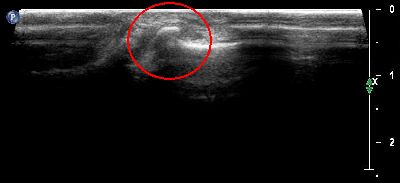

Esostosi scafoidea esostosi scafoidea